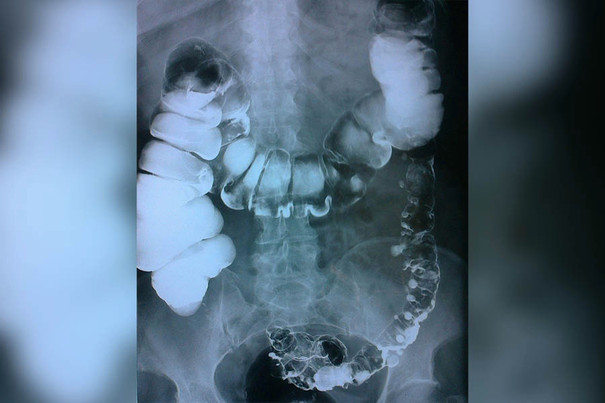

— Ребенка переводят в  ОДКБ уже в  тяжелом состоянии. Уже тут врачи хирургического отделения ставят мальчику диагноз  — кишечная непроходимость, перекрут дивертикула Меккеля, заворот брызжейки подвздошной кишки,  — сообщают в пресс-службе регионального минздрава. —   Врачи  провели лапаротомию. Сделали резекцию  — и  удалили часть кишечника, вызвавшую это состояние маленького пациента.

Дивертикул Меккеля  — это распространенная врожденная аномалия желудочно-кишечного тракта. В  50% случаев заболевание обнаруживается у  детей до  10  лет. С  развитием компьютерной томографии появилась возможность выявлять и  дифференцировать заболевание и  его осложнения на  дооперационном этапе. Сам по  себе дивертикул не опасен, однако он  может стать причиной развития заболеваний, требующих немедленного хирургического вмешательства. У  детей клиническая картина дивертикулита Меккеля часто похожа на  аппендицит.